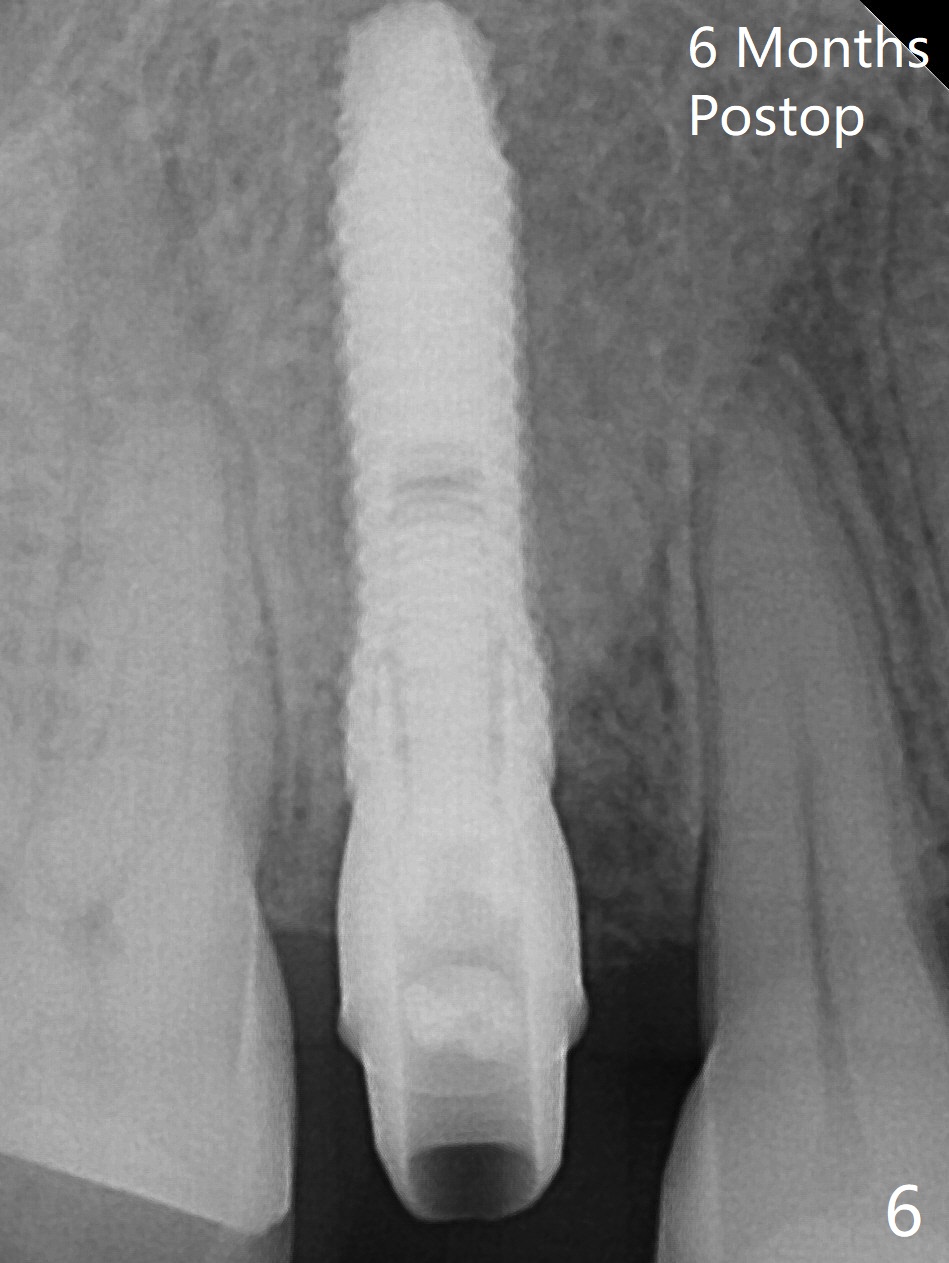

After extraction of residual root at #4 with mesiopalatal subgingival margin (Fig.1), the mesiopalatal crestal bone loss is noted. Instead of the mesial slope, the initial point of the osteotomy is at the mesial and middle (buccopalatally) of the socket bottom (Fig.2, 2'). The initial depth with 2 mm drill is 20 mm (gingival level), while the last drill (3 mm) is used for 17 mm (because of soft bone). When a 3.8x16 mm implant is placed (Fig.3,4), the distal gap of the socket is closed, suggesting that the implant moves to the least resistant area. However, it is favorable to the mesial crestal defect (Fig.4). The buccopalatal position of the abutment (4.5x4(4) mm) is a little too palatal (Fig.5, taken prior to provisional fabrication). The implant seems to have osteointegrated 6 months postop (Fig.6).